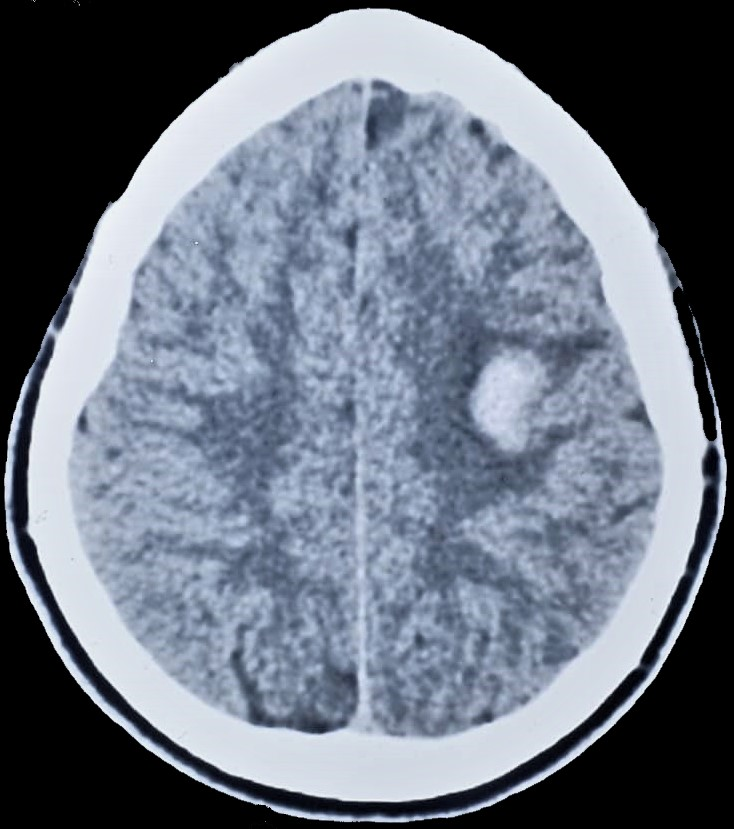

Neuroimaging studies were also done: Brain MRI, which reported a well-defined, rounded, T1 heterogeneous, (central core of iso intensity to grey matter with a rim of hyperintensity), collection measuring (2.5TR x 2.5AP x 2.5CC) cm in the left parietal lobe (Figure 1). This collection ‘blooms’ on T2/ SWI imaging by suggesting early subacute haemorrhage (Figure 2). There was surrounding vasogenic oedema, No enhancement was seen post-gadolinium administration and does not ‘restrict’ on DWI/ADC imaging. On a complementary Brain CT Scan done 2 days later was described as a hyperdense collection (mean attenuation of 58HU) in the left parietal lobe with minimal surrounding oedema. No significant mass effect or shift of midline structures is seen. Findings in-keeping with early left parietal lobe subacute haemorrhage (Figure 3).

Figure 3 Brain CT scan-Left parietal hyperdense collection with minimal surrounding edema.